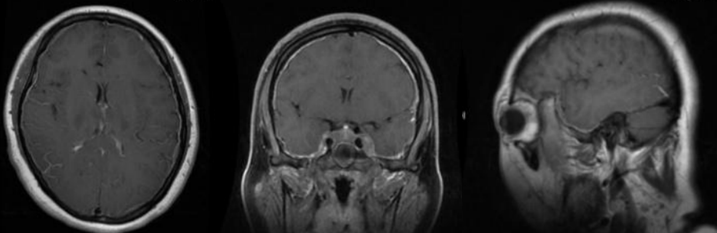

34岁男性,体检发现颅内占位。

image015.png

答案:小脑血管母细胞瘤。血管母细胞瘤是最常见的小脑原发肿瘤,多见于青壮年。可为多发,约20%的血管母细胞瘤患者伴有视网膜血管瘤,同时6%的视网膜血管瘤亦伴有小脑的血管母细胞瘤。肿瘤同时发生于颅内及视网膜时称为von-Hippel-Lindau(vHL)病,该病为常染色体显性遗传的家族性肿瘤性疾病,可伴有多脏器(肾脏、胰腺、睾丸等)的肿瘤和囊肿。根据肿瘤的形态特点,可分为单纯囊型、囊结节型和实质型,以囊结节型最多见。

MRI表现:T1等信号结节,可见流空效应;T2和FLAIR高信号的囊变和结节,可能有高信号的瘤周水肿;强化MRI:结节明显强化;囊性部分无强化,囊壁常无强化效应;DWI相:囊性成分在DWI为高信号,ADC为低信号。